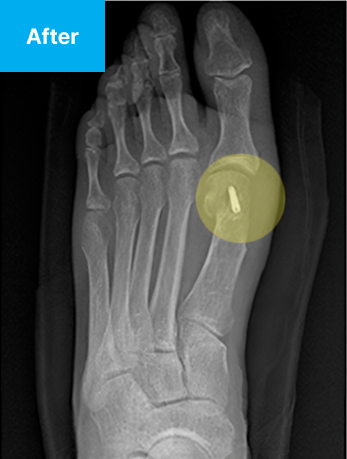

최소침습 무지외반 교정술이란?

경증에서 중등도의 무지외반증 환자를 대상으로,

환부에 약 2mm 크기의 구멍을 2~4개 뚫어 변형된 뼈를 교정하는 수술법입니다.

부분마취 후 최소 2mm 최소 피부절개(구멍2~4개)를 시행한 뒤, 실시간 방사선 영장장치 보면서

특수 기계를 넣어 변형된 뼈를 세밀하게 절골하고, 절골한 뼈를 올바른 배열로 배치합니다.

B-ita(바른마디병원 미타)

• B-ita 바른마디병원 미타 최소침습 수술

• 2~4mm

• 불필요

• 적다

• 빠르다

• 낮다

• 빠른 복귀